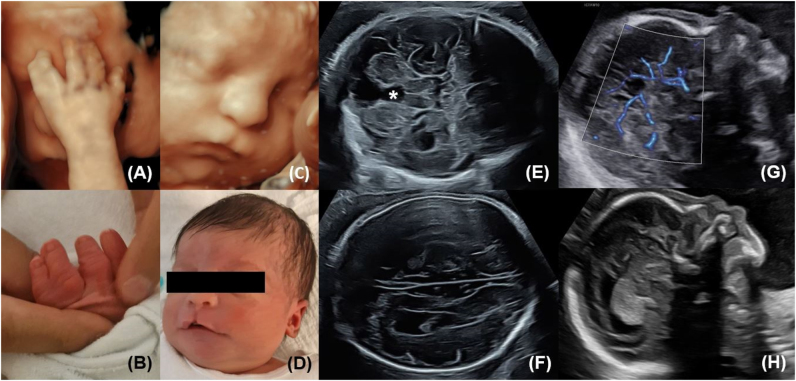

Case presentation: In the present case, a routine second trimester scan revealed cerebral abnormalities (corpus callosum agenesis, cerebellar cleft due to vermian hypoplasia, ventriculomegaly), suspected cortical developmental disorder, hypertelorism, a hypoplastic nasal bone, a small median cleft lip and palate, abnormal facial profile, as well as syndactyly of the left hand involving the fourth and fifth finger. Genetic testing revealed a normal karyotype. Subsequent trio exome sequencing did not identify any pathogenic variants or variants of unknown significance. The vaginal delivery at term and postnatal adaptation were uneventful. Postnatal neurosonographic imaging and clinical evaluation confirmed the prenatal findings. Both mother and child were discharged in healthy condition with scheduled follow-ups. Differential diagnoses of the present anomalies include Hartsfield-Bixler-Demyer Syndrome, Oro-Facial-Digital-Syndromes, Ectrodactyly Ectodermal Dysplasia Cleft Lip/Palate Syndrome and Acrocallosal Syndrome.